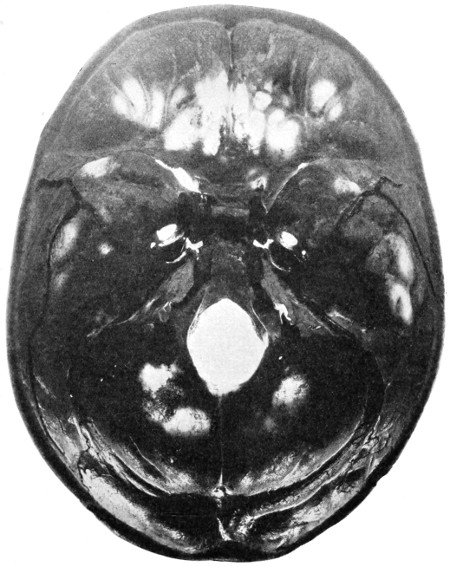

| 50 A and B. The inner aspect of the skull and the same seen on transillumination | 137 |

| 51. To illustrate compression of the brain as produced by an extra-dural hæmorrhage from the middle meningeal artery[x] | 141 |